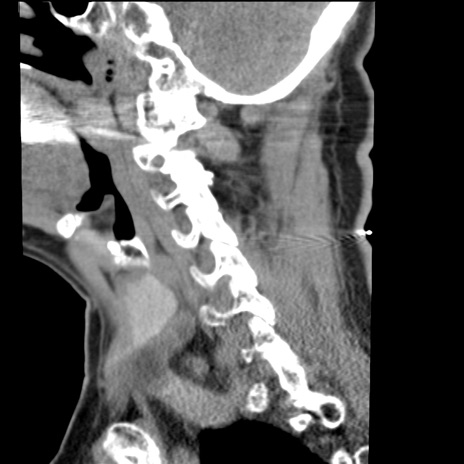

症例50 頚椎CT(矢状断像)

【症例】60歳代女性

【主訴】後頭部〜右後頸部にかけての痛み

【現病歴】本日飲食店でコーヒーを飲んでいたところ、突然後頭部〜右後頸部にかけて痛みが出現し、右上肢の感覚障害を伴ったため救急要請。

【身体所見】脳神経学的に明らかな異常所見を認めず。右上肢に軽度の感覚障害あり。

異常所見と診断は?

頚椎CT